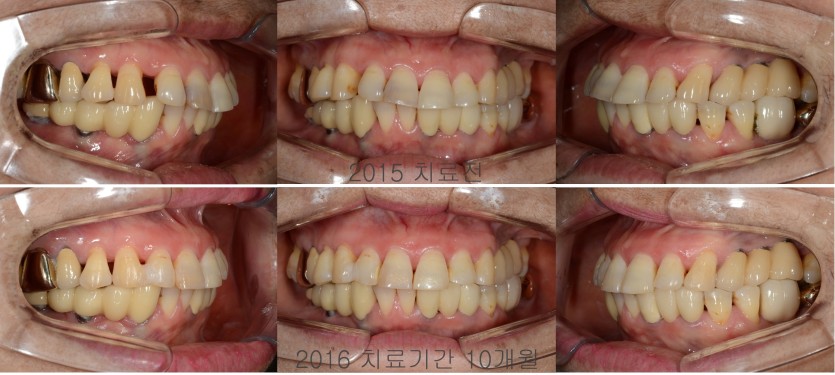

실버세대의 벌어진 앞니 교정치료 301회

노년기에 접어들면서 치주염이 진행되고

치아를 잡아주고 있는 치주조직과 치조골에 염증이 생기면

치아가 움직이면서 치아사이가 벌어지게 됩니다.

이러한 병리적 치아이동이 일어난 경우에는

교정치료에 선행하여 치주염 치료가 진행되어야 합니다.

노년기의 교정치료는 일반 교정장치를 사용하는 것에 부담을 가지시는 경우가 많아서

투명교정장치를 이용해 치료를 진행하고 있습니다.

은퇴를 하시고나서 인생의 후반부를 자신있게 보내시고 싶은 분들께 교정치료를 추천드립니다.